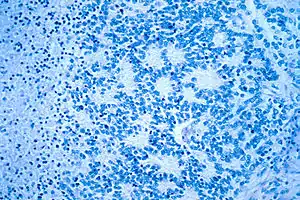

| Microscopic view of a typical neuroblastoma with rosette formation | |

On microscopy, the tumor cells are typically described as small, round and blue, and rosette patterns (Homer Wright pseudorosettes) may be seen. Homer Wright pseudorosettes are tumor cells around the neuropil, not to be confused with a true rosettes, which are tumor cells around an empty lumen.[28] They are also distinct from the pseudorosettes of an ependymoma which consist of tumor cells with glial fibrillary acidic protein (GFAP)–positive processes tapering off toward a blood vessel (thus a combination of the two).[29] A variety of immunohistochemical stains are used by pathologists to distinguish neuroblastomas from histological mimics, such as rhabdomyosarcoma, Ewing's sarcoma, lymphoma and Wilms' tumor.[30]

Neuroblastoma is one of the peripheral neuroblastic tumors (pNTs) that have similar origins and show a wide pattern of differentiation ranging from benign ganglioneuroma to stroma-rich ganglioneuroblastoma with neuroblastic cells intermixed or in nodules, to highly malignant neuroblastoma. This distinction in the pre-treatment tumor pathology is an important prognostic factor, along with age and mitosis-karyorrhexis index (MKI). This pathology classification system (the Shimada system) describes "favorable" and "unfavorable" tumors by the International Neuroblastoma Pathology Committee (INPC) which was established in 1999 and revised in 2003.[31]